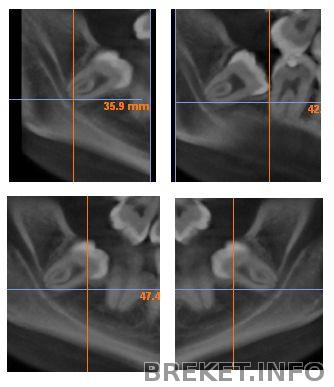

Вот они, мои очаровашки справа...

Трубочка под зубом - это мой нерв. Наверно правильнее сказать что зуб не близко от нерва, а сидит в нём... Лучше сделать панорамные снимки не получилось (у меня 3D)